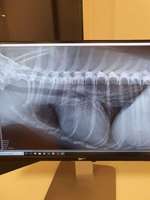

Paula ist gegen 5 Uhr aus dem Bett gesprungen und hat sich übergeben, ein Stück Knochen und Gras, danach fing sie an zu würgen, auf einmal rannte sie durchs Zimmer, sprang ins Bett, fing an zu zucken und zittern hat Maul und Augen g ...